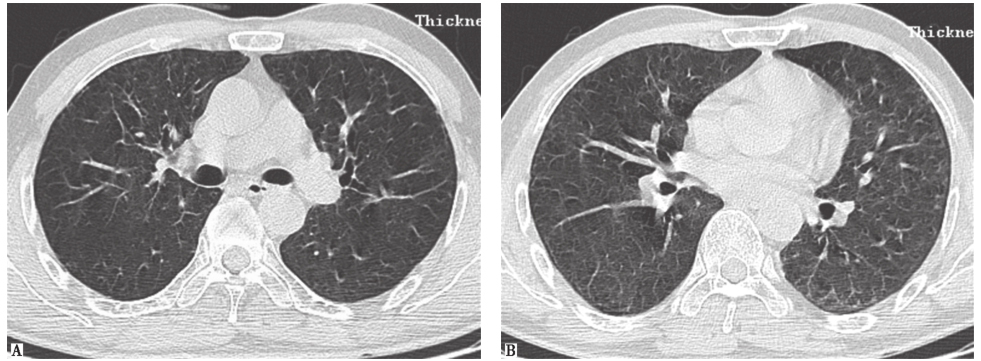

外院胸部CT示两肺散在磨玻璃影、弥漫性小结节影(图1),局部可见牵拉性支气管扩张。

图1外院胸部CT表现

两肺散在磨玻璃影及小结节影(图13),局部网状影,较入院前(图1)明显吸收、好转。

图13入院后胸部HRCT表现

患者入院后所做系列检查显示:①自身抗体均阴性,结合临床表现,基本可排除风湿免疫病;②常规病原学检查均阴性;③胸部HRCT可见两肺小结节影、磨玻璃影,较外院CT明显吸收、好转,证明外院激素治疗有效。此外,患者在未接受抗肿瘤治疗的情况下小结节影吸收、好转,与肺转移癌不符(由于癌细胞不断增殖,粟粒状癌灶可在短时间内渐进性增大)。